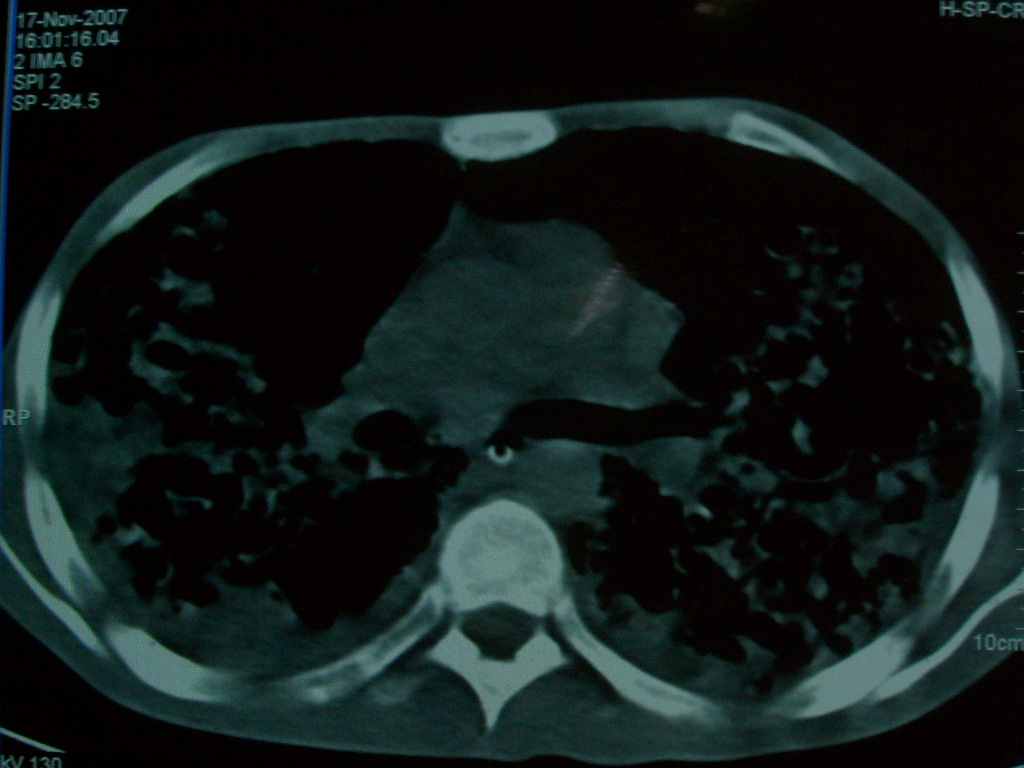

标题: CT10510:男.18岁,咳嗽咳痰两月.(有病理) [打印本页]

标题: CT10510:男.18岁,咳嗽咳痰两月.(有病理)

双肺布满大片状实变及网格状结节影,内参杂大小不等的气囊及空气支气管征,心脏增大。考虑:1 全身结缔组织疾病—系统性红斑狼仓?2 肺泡蛋白沉积症合并感染!

双肺布满大片状实变及网格状结节影,内参杂大小不等的气囊及空气支气管征,双侧胸膜腔少量积液,双下肺近膈面透亮度尚可,病人较年轻,病变较重(不知为什么上胃管?)考虑:1.胶原病肺部改变,2.组织细胞病x。结合实验室检查。

首先考虑组织细胞x病。两肺中上肺野多发囊腔,中下肺野内见多发小结节,并可见肺间质增厚。患者是男性,年龄较小。胶原性病变比较多见的类风湿、系统性红斑狼疮和硬皮病临床和影像均不是很支持,类风湿和系统性红斑狼疮的肺部表现最常见的是胸腔积液,硬皮病可见食管的扩张。

肺内多发斑片状、结节状、融合大片状及网格状影,多发薄壁空腔影,胸膜肥厚,纵隔、气管右移,考虑ⅲ型肺结核,多发空洞,继发肺间质纤维化。

双肺结核并播散.患者以肠梗阻入院,手术为肠结核.术后咳嗽做ct检查.